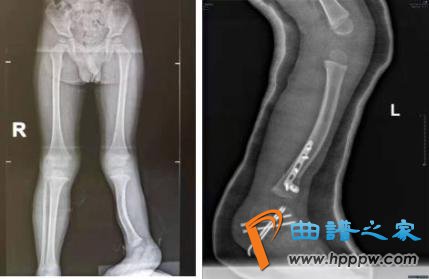

我院骨科团队在经前期PICU医护团队生命支持后联合麻醉科、手术室,成功救治首例高空坠落致全身多发性骨折患儿。